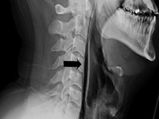

• Holding Back A Sneeze Ruptured A Man's Throat!

Holding Back A Sneeze Ruptured A Man's Throat!